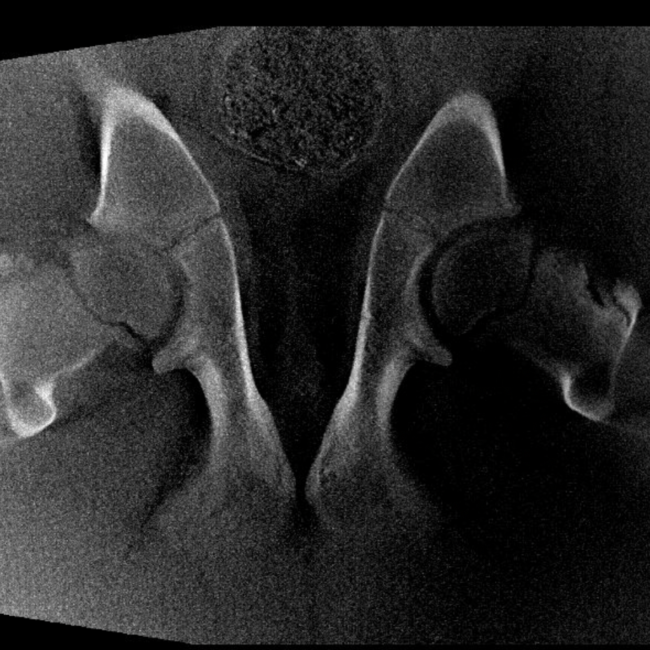

Our High Definition Volumetric Imaging (HDVI) technology represents the most advanced stage of Flat Panel CT technology. It offers exceptional diagnostic imaging for both hard and soft tissues, in diagnostic settings and intraoperative theaters. It is the gold standard for orthopedic applications.

Pegaso enhances safety and usability by enabling the scanning of a standing horse’s head, neck, and limbs.

Scan of the standing horse

Pegaso scans head, neck and limbs of the standing horse